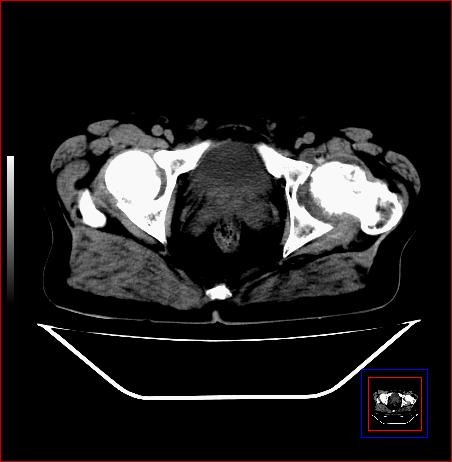

标题: CT15143:髋关节结核?

男,49,髋关节疼痛1年,无肺结核。

支持左侧髋关节结核合并轻度半脱位

骨质破坏,硬化,周围软组织脓肿,支持骨结核

骨质破坏,硬化,周围软组织脓肿,关节间隙增宽,支持骨结核

骨质破坏,硬化,周围软组织脓肿,关节间隙增宽,支持骨结核 .应与无菌坏死鉴别

可以是结核,也可以是无菌坏死,还可以是先天髋关节脱位,不结合临床病史,只凭图像鉴别,请各位老师指教。